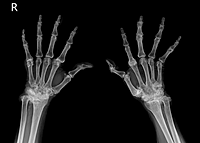

류마티스 관절염(RA)은 신체 전체에 관절통과 손상을 유발할 수 있는 자가 면역 질환입니다. 이 질환은 보통 신체 양쪽에서 동일한 관절에 영향을 주기 때문에, 한쪽 팔이나 다리의 관절이 영향을 받으면 반대쪽도 동일한 영향을 받을 수 있습니다. 이러한 특징은 의사들이 류마티스 관절염을 다른 형태의 관절염과 구별하는 데 도움이 됩니다.

조기에 진단할수록 치료 효과가 크기 때문에, 류마티스 관절염의 초기 증상을 알고 있는 것이 매우 중요합니다. 이 질환은 활막이 존재하는 모든 관절에서 발생할 수 있으며, 자가면역 이상으로 인해 외부 공격으로부터 신체를 보호하는 면역체계가 오작동하게 됩니다. 우리나라에서는 전체 인구의 약 1%가 류마티스 관절염을 앓고 있는 것으로 알려져 있습니다. 초기 증상은 눈에 잘 띄지 않으며, 통증과 뼈마디 변형이 발생한 후에야 발견될 수 있습니다.